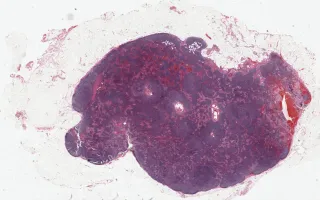

Lymph node, In situ follicular neoplasm, H&E stain

In situ follicular neoplasm, formerly known as follicular lymphoma in situ (FLIS), is defined as the presence of BCL2+/CD10+ neoplastic follicles in a background of reactive germinal centers. The neoplastic follicles are predominately composed of monoclonal centrocytes, which carry the t(14;18) IGH/BCL2 translocation. Given their indolent nature, the name "intrafollicular neoplasia" has been proposed as an alternative terminology. The differential diagnosis of FLIS includes partial involvement of the lymph node by FL (PFL). Studies have shown that only 5% of the patients with FLIS will develop or have concurrent FL; on the other hand 53% of the PFL will progress to FL if left untreated.

This slide shows H&E stain. See Related Content for CD10, BCL2, and BCL6 stains.